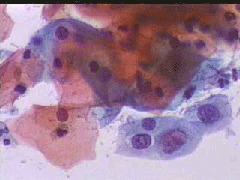

Papanicolaou test 15.12.2004

Πλακωδη επιθηλιακά κύτταρα κυρίως της επιφανειακής και λιγώτεροτης διαμέσουστιβάδας. . Λίγα της παραβασικής καθώ και πολύλίγα του ενδοτραχήλου .. Σε πολλάοπτικάπεδία ομάδες κυττάρων της παραβασικής και λιγων της διαμεσου στιβαδος, με διογκωμένους, αρραιοχρωματικούς και ανισομεγέθειςπυρήνες, με καλή δομήχρωματίνης. Kαθαρό υπόστρωμα. Yπόνοια για δυσπλασία σοβαρού βαθμού (CIN II-III)